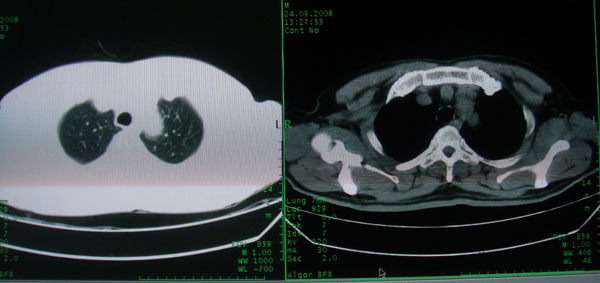

患者男性58岁因二周前起咳嗽,今天胸片示左上肺占位性病变行ct检查,无发热,无咯血痰.

左上肺感染性病变,结核伴空洞形成可能,左上肺膨胀不全

左肺上叶病灶,实变但见含气支气管、空洞但未见壁内结节及积液;

考虑:①感染性病变(包括特殊感染型肺tb)

②肿瘤性病变(考虑患者年龄比较大的关系/所以不排除)

初学者。。。左肺空洞性病变,并可见阻塞性肺不张改变,鉴于患者为老年男性,且临床症状仅有咳嗽,全身中毒症状不明显,所以我首先考虑为左肺癌性空洞并左侧肺门淋巴结转移伴左肺阻塞性肺不张。结核性空洞放于第二位考虑,可以进行相关实验室检查。希望能有病理结果,谢谢!!!!!

左肺上叶实变影,内见支气管充气征及空洞影,病人年龄较大,无发热及结核中毒症状,心影左移,未见纵隔淋巴结肿大;不知实验室检查结果如何?有否嗜酸细胞增多,有没有进行治疗?就目前资料首先考虑1.感染性病变,2.慢性嗜酸性肺炎?可结合实验室检查并短期治疗复查,肺癌不能排除。